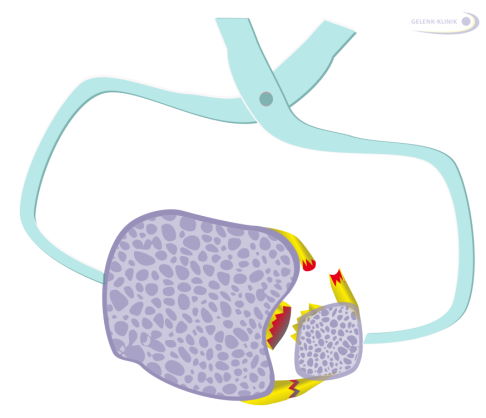

Knöcherner Ausriss der Syndesmose: eine besondere Herausforderung

Weiterhin sind knöcherne Ausrisse der Syndesmose im vorderen, hinteren oder im interossären Bereich möglich. Diese Verletzungen haben eine besondere Relevanz für die Therapie. Diese knöchernen Verletzungen sollte man im Rahmen der Frakturversorgung oder auch bei einer notwendigen Revision möglichst genau wiederherstellen, um Fehlstellungen der Sprunggelenksgabel zu vermeiden.

Bei nicht optimaler Wiederherstellung der Knochenstellung (Reposition) nach knöchernem Ausriss der Syndesmose ergeben sich fast unvermeidbar Folgeschäden. Meist resultiert eine bleibende massive Syndesmoseninstabilität. Ob eine Operation angeraten ist, hängt immer auch von der Größe der Bandfragmente ab und wie genau der Ausriss verläuft.

Ein Syndesmosenausriss kann mit der Ablösung von Knochenfragmenten verbunden sein: Man spricht beim vorderen Ausriss an der ventralen Seite des Schienbeins vom "Tubercule de Tillaux Chaput" und beim wadenbeinseitigen Ausriss vom "Wagstaffe-Fragment". Beide Knochenfragmente können mit Schrauben refixiert werden.